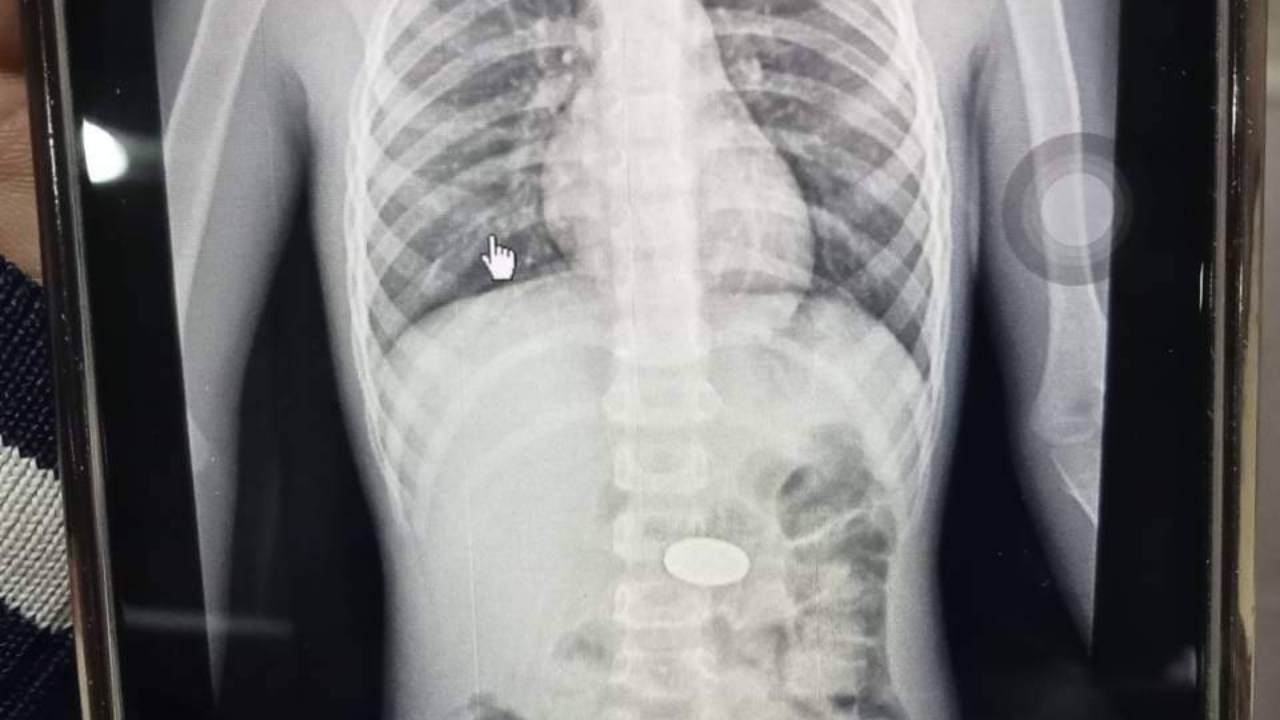

จากนั้น ได้เอามือล้วงเข้าไปมือไปโดนเหรียญ แต่ไม่สามารถเอาออกได้ จึงรีบพาไปส่งโรงพยาบาลละหานทราย เมื่อไปถึงโรงพยาบาล ลูกชายอาการดีขึ้นเป็นปกติ แต่เหรียญยังไม่ออก แพทย์จึงเอาตัวไปเอกซเรย์ พบว่าเหรียญอยู่ในช่องหลอดอาหาร โดยหมอแจ้งว่า โชคดีที่เหรียญเข้าไปในหลอดอาหาร หากเข้าไปที่หลอดลม มีโอกาสเสียชีวิตได้สูง หมอจึงเอายาถ่ายมาให้เพื่อให้ขับถ่ายออกมา แล้วสั่งให้ดูแลอย่างใกล้ชิด หากมีอาการผิดปกติให้รีบไปส่งโรงพยาบาลทันที